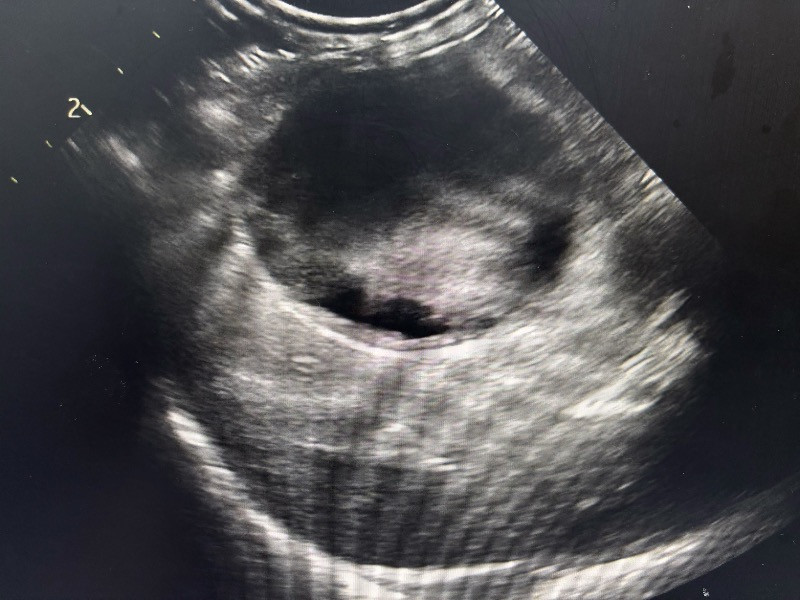

妍兒 2025-09-29 她剛開完拆膽䉴手術 跟拆脾藏 過了五天出院⋯ 愛犬睡到凌晨三點走了 請問是腎上腺腫瘤破裂造成休克嗎? 他的醫生是這樣說!還說腫瘤不能開刀她13歲了 、還有腫瘤位置也不能開刀旁邊有大血管! 真的好難過 懇請有醫生知道能跟我說ㄧ下 腎上腺腫瘤破裂真的會造成死亡嗎? 姚勝隆 院長 2025-10-07 治療中或術後的動物,建議與主治獸醫師多討論,只有主治獸醫師最清楚寵物的病況。 1 分享–– 我也要提問